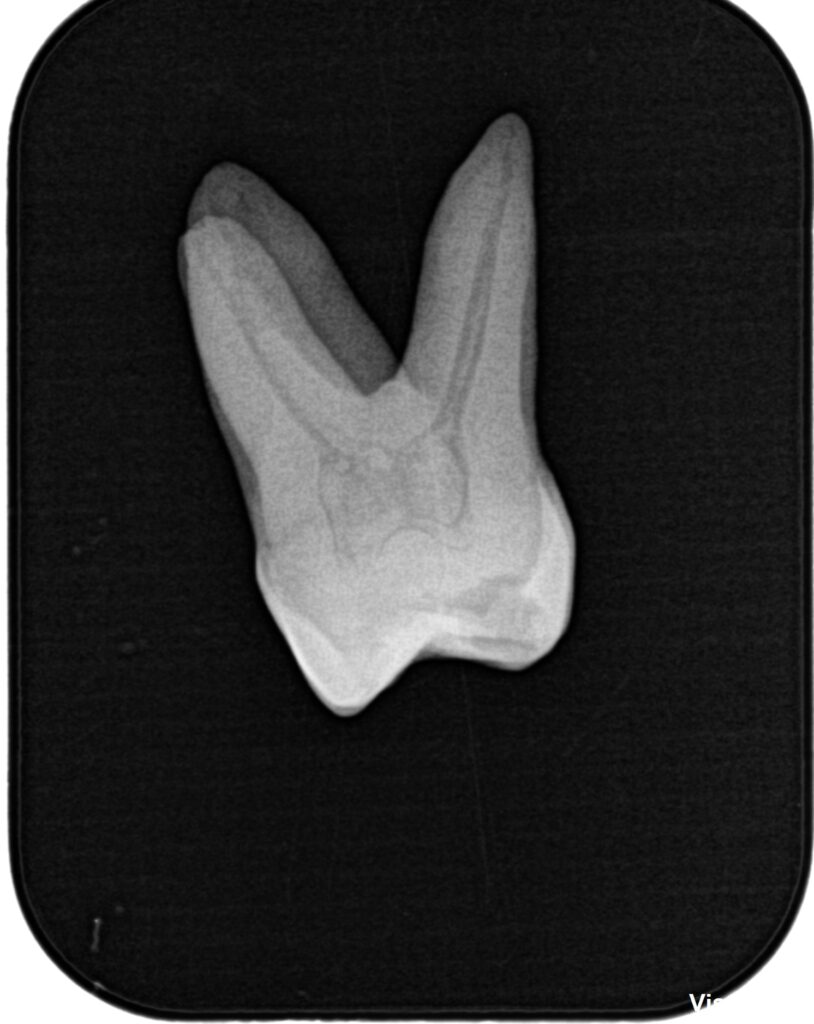

まず作業長の測定方法を行うまでを解説した。

その後、根管形成である。

日曜日は実習を行った。

土曜日の内容を投影した実習であった。

2本の歯牙で実習し、あっという間に1日は終了した。